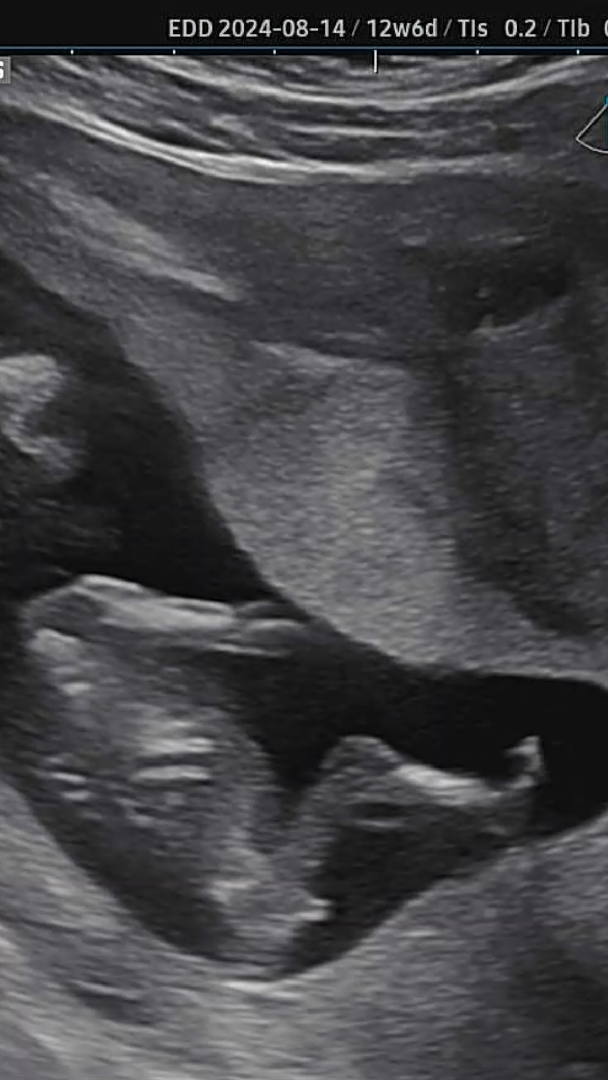

각도법 봐주세여..!

척추와 꼬츄 각도를 봐야한다는데, 저게 꼬츄가 맞는 지도 모르겠네용ㅋㅋㅋ 혹시 요 사진으로 판별이 가능할까요?